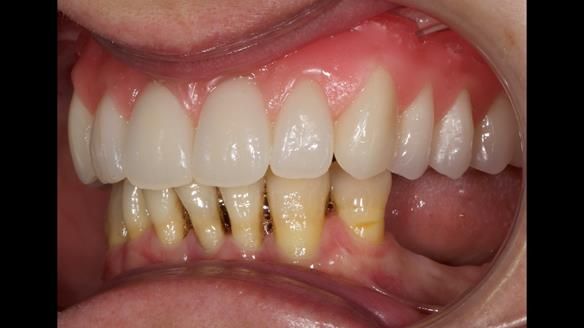

She had previously suffered from generalised periodontitis – stage IV, grade C, currently stable, with reduced attachment across the upper arch.

By the time she came to me, her periodontal condition was stable — but the aesthetics in the upper jaw were very poor.

Dr Syed Abad — my colleague and a Specialist in Periodontics — had successfully stabilised her gum health.

We provided her with an immediate upper denture (Mk 1), followed by a definitive metal-based upper denture (Mk 2). A lower removable partial denture was discussed, to be made only if needed once the upper treatment was complete. However, at review, this wasn’t necessary — Adnana had excellent neuromuscular control and function, even with a shortened dental arch (SDA).